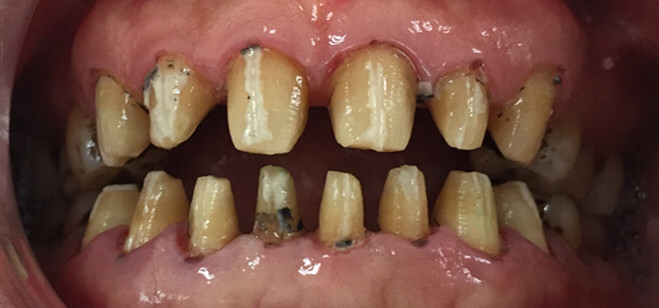

前牙区的美观与功能并重!一口洁白整齐的牙齿几乎是每个人的梦想,然而实际生活中却因为种种客观的或是主观的因素让很多人羞于开口微笑!今天我们来浅谈一下前牙区美学修复的基本概念和几种具体的实用修复方案!

一、前牙美学修复:是指通过临时或者永久的修复体恢复前牙应有的形态和美学色泽。

二、具体的修复方案大致分为三类:

1、全瓷冠修复:适用于外伤冠折及前牙根管治疗后基牙变色的前牙修复!

2、瓷贴面修复:适用于四环素牙、釉质发育不全、牙列轻度拥挤和前牙区先天缝隙过大的美容修复!可短时间内还患者自信优雅的笑容。

3、种植修复:适用于前牙外伤缺失的病例!即刻修复或即刻负重能有效帮助患者建立良好的生活信心,使其在正常的工作和生活中不影响和他人的沟通!